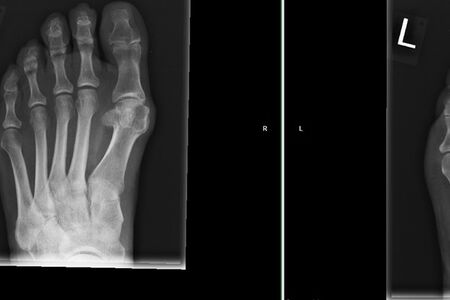

Therapie: distale Umstellung am MT1, Osteotomie an MT 2-4

Die operative Korrektur, bei der Umstellungsosteotomien an den Mittelfußknochen 1-4 links durchgeführt wurden, erfolgte im Mai 2018.

Eine CT Untersuchung ergab eine zeitgerechte Knochenheilung.

Bei anhaltenden Beschwerden wurde im Mai 2019 eine Röntgenaufnahme durchgeführt, die einen Schraubenüberstand von 1mm am Köpfchen des MT3 ergab. Dieser Befund wurde durch eine CT Untersuchung, bei der zusätzlich eine Arthrose im Grundgelenk der Großzehe und der zweiten Zehe gefunden wurde,  bestätigt.

Röntgenuntersuchungen